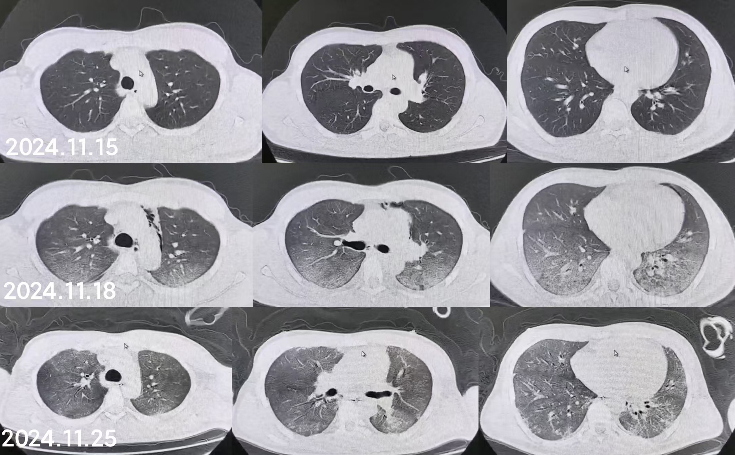

同时给予镇痛、镇静联合肌松,去甲肾上腺素泵入维持血压,俯卧位通气,B某入院后出现高热,经验性给予美罗培南联合万古霉素抗感染治疗,后降阶梯调整为哌拉西林他唑巴坦联合万古霉素治疗;C某抗感染方案为经验性使用万古霉素联合哌拉西林他唑巴坦治疗,痰培养出鲍曼不动杆菌后改为替加环素、头孢哌酮舒巴坦及万古霉素治疗;根据《刺激性气体中毒诊治专家共识》[5]中关于重症患者的治疗措施,同时给予2人泮托拉唑抑酸护胃,氨溴索、富露施化痰、甲泼尼龙抗炎、西维来司他纳及乌司他丁清除炎性介质,维生素C抗氧化、保肝、输血补液,纤支镜吸痰及肺泡灌洗,维持水电解质平衡及营养支持治疗,特别考虑到肺损伤情况,在使用有创通气时给予超保护性通气策略[5, 7];2人仍先后出现气胸、纵膈气肿,行胸腔闭式引流;持续V-V ECMO治疗15 d后,肺部纤维化不可逆转,高分辨率CT肺纤维化评分 > 75%(图 3、4),符合终末期肺病标准,有肺移植指征[8],经评估后2人顺利完成病变肺组织切除(图 5),双侧序贯肺移植,术后患者复查胸片肺部恢复正常(图 6),2位患者术后气管切管接呼吸机辅助通气,并给予泼尼松、他克莫司、吗替麦考酚酯抗排异治疗,其余根据病情给予万古霉素调节肠道菌群、抗感染、保肝、抗凝、呼吸康复锻炼等治疗,后顺利脱机、拔除气切套管,病情稳定出院,后续规律复查胸部CT(图 7)恢复良好。

| 图 3 B某发病15 d时胸部CT表现 |

| 图 4 C某发病15 d时胸部CT表现 |